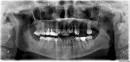

Последнее время меня беспокоит с левой стороны, самый крайний зуб. В этом зубе 2 года назад был удален нерв и запломбированы все каналы. Недавно буквально на днях лечила передний зуб. Тоже проводилось удаление нерва, и после установка постоянной пломбы. Между крайним слева зубом и передним какие-то зубы лечили, какие-то нет. Но ноющие ощущения не проходят и они ближе к крайнему зубу (кажется это 7-ка). Снимок, к сожалению, не новый. Возможно, болит не зуб, а десна. Мажу эту часть десны Метрогил Дента и Холисалом.

Можно ли по снимку сказать, есть ли среди нижних зубов слева там, где нерв не удален, воспаление?

На нижней челюсти слева удалены нервы в 36-ом зубе, но каналы запломбированы не до верхушки корня. Соответственно, зуб может давать болевую реакцию. Рекомендуем Вам сделать прицельный снимок 36-го зуба и, если возможно, перелечить каналы.